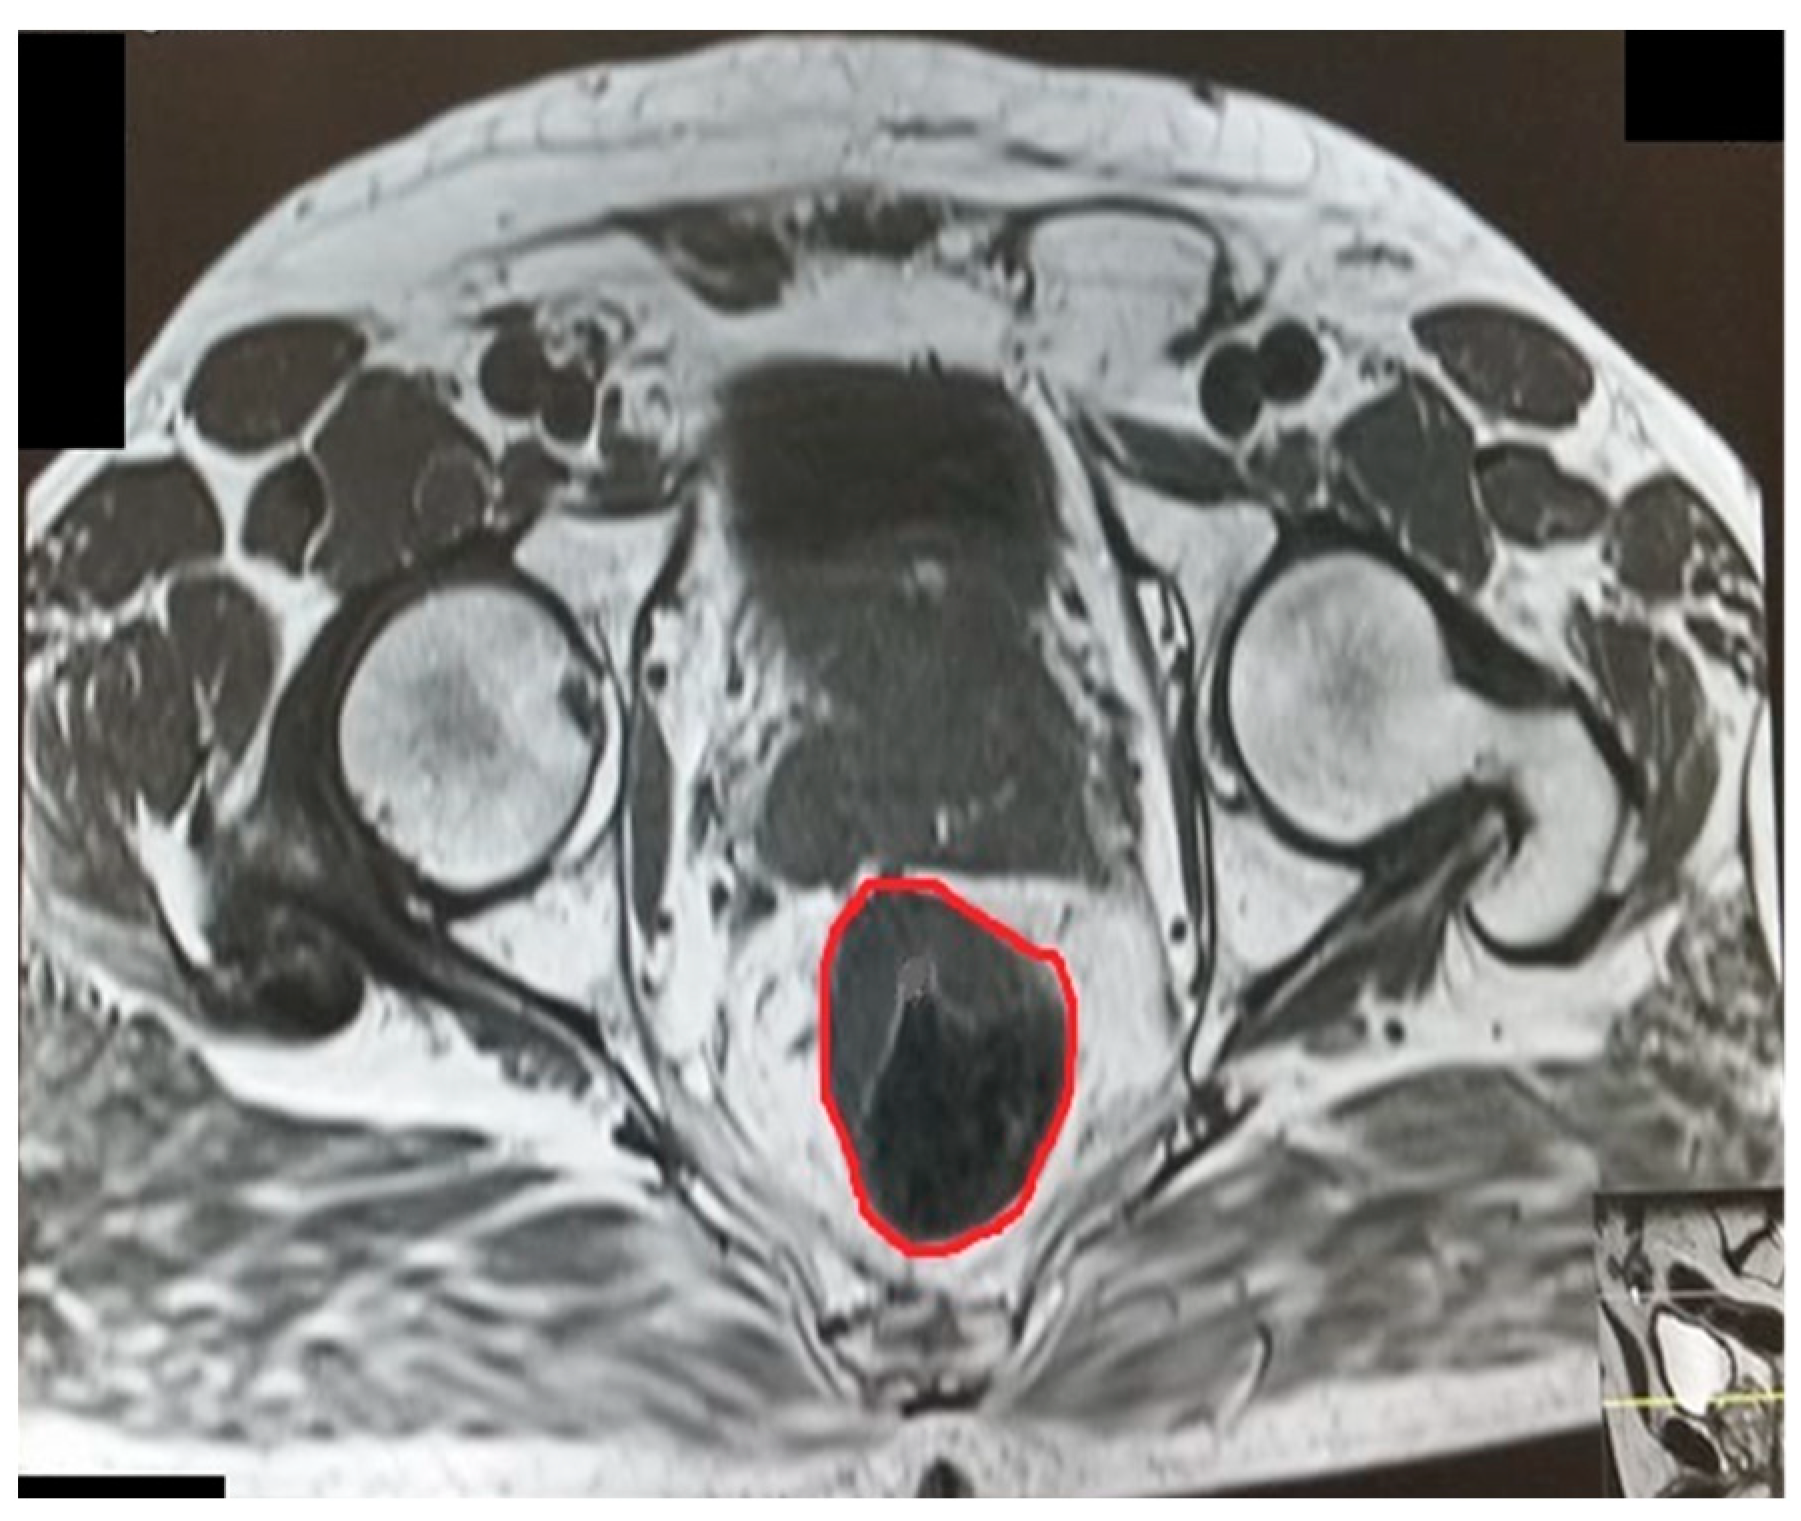

Figure 5.

Intertuberous distance.